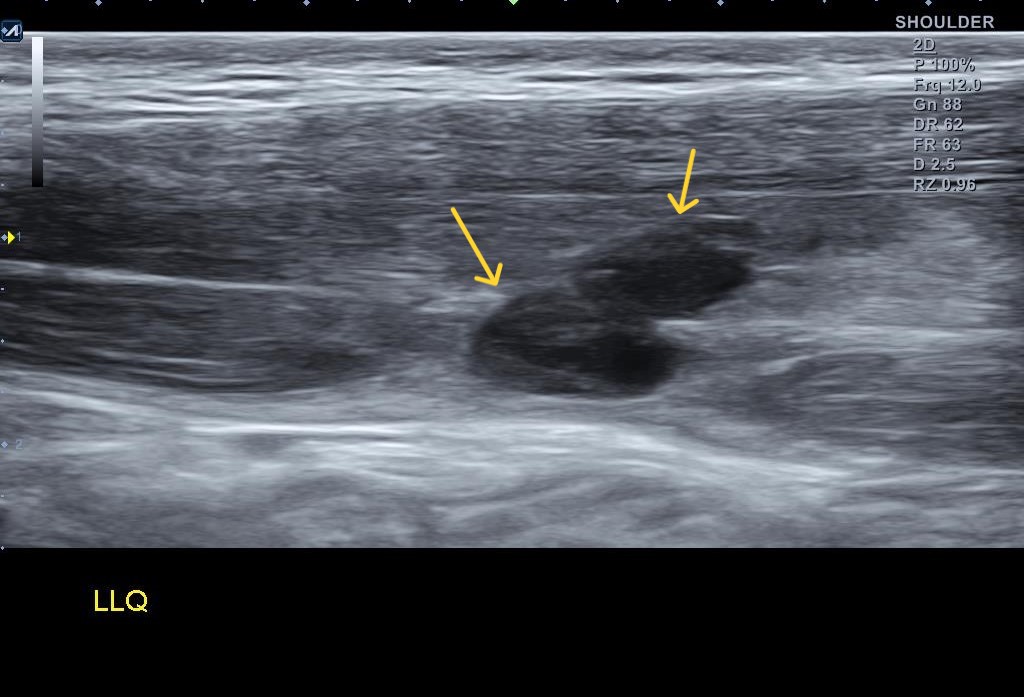

당산 정형외과, 당산역 정형외과, 영등포 정형외과안녕하세요 오늘은 '석회성 건염' 치료 사례를 좀 보여드리려고 합니다. 이전에 한번 석회성 건염의 치료 결과를 보여드린 글이 있습니다.[박상준원장/통증이야기] - 석회성 건염은 완치될 수 있을까? 석회성 건염은 완치될 수 있을까? (당산 정형외과, 당산역 정형외과, 영등포 정형외과)안녕하세요 당산 정형외과 박상준의원, 박상준 원장입니다. 오늘은 석회성 건염에 관한 이야기를 해볼까 합니다. 진료실에 있다보면 갑작스런 관절 통증으로 찾아오시는 분들이 많습니다. 갑작fitnessworld.co.kr오늘도 석회성건염을 석회 흡입술 + 체외 충격파로 치료된 분들의 케이스를 보여드리도록 하겠습니다.(1) 갑자기 어깨가 아파서 온 환자이분은 60세 정도된 남자 분..